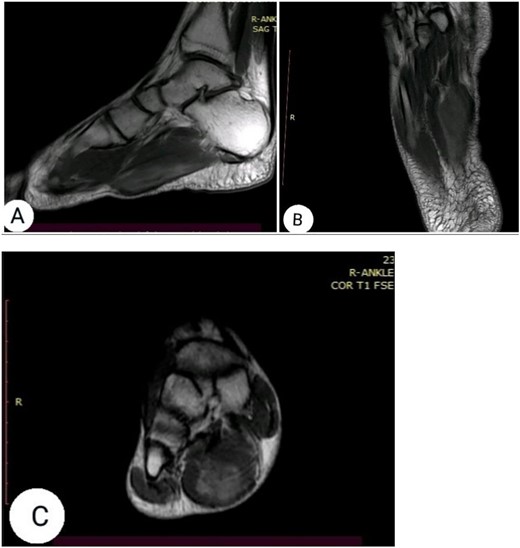

The clinical examination revealed flexion contracture of the third digit of the right foot with dislocation of the proximal interphalangeal (PIP) joint, limited passive and active extension of the second and fourth digits and the presence of little thickness in the skin over the dorsal aspect of the first metatarsophalangeal joint of the foot (Fig. 1). By palpation, there is a non-tender pseudotumor within the plantar aspect of the right foot, without any scare over it (Fig. 2). The X-ray radiographs show inferior dislocation of the PIP joint of the third digit, without any signs of bone lesions or previous fracture (Fig. 3). Ultrasound echomyography shows a significant and heterogeneous increase in the size of the Flexor Digitorum Brevis muscle of the foot. Magnetic resonance imaging (MRI) before gadolinium injuction (Fig. 4) and after gadolinium injuction (Fig. 5) shows a heterogeneous hyperenhancement with irregular margins within the Flexor Digitorum Brevis muscle.

(A) sagittal T1-weghited, (B) axial T1-weighted and (C) coronal T1-weighted MRI following gadolinium injection showing hyperenhancement within the muscle tissue.